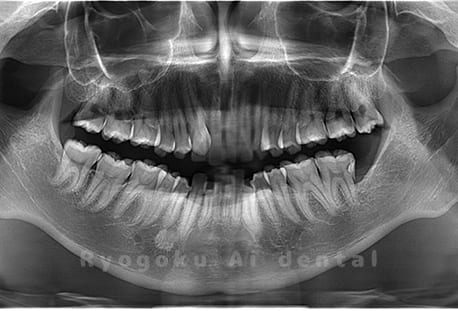

Case02

-

- 原因

- 下顎の水平埋伏智歯

- 治療内容

- 下顎の水平埋伏智歯を抜歯

<リスク・副作用>

手術後は痛み、腫れ、痺れなどの副作用が生じる場合があります。